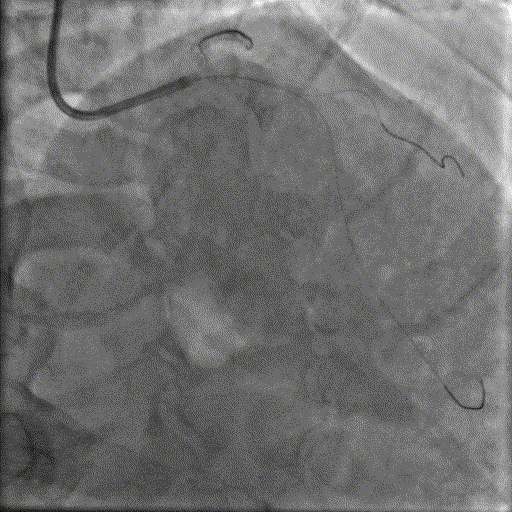

于LM-LAD依次植入两枚药物洗脱支架,经非顺应性球囊后扩张支架,复查造影&IVUS提示血管内钙化仍较重,支架贴壁不良,遂再次启动IVL治疗。

再次冲击波球囊治疗

3.0*12mm@4atm 冠脉血管内冲击波导管反复进行5个周期治疗,并选取后扩张球囊对病变行扩张治疗。最终复查造影提示残余狭窄小于10%,未见夹层及血肿,TIMI血流3级。